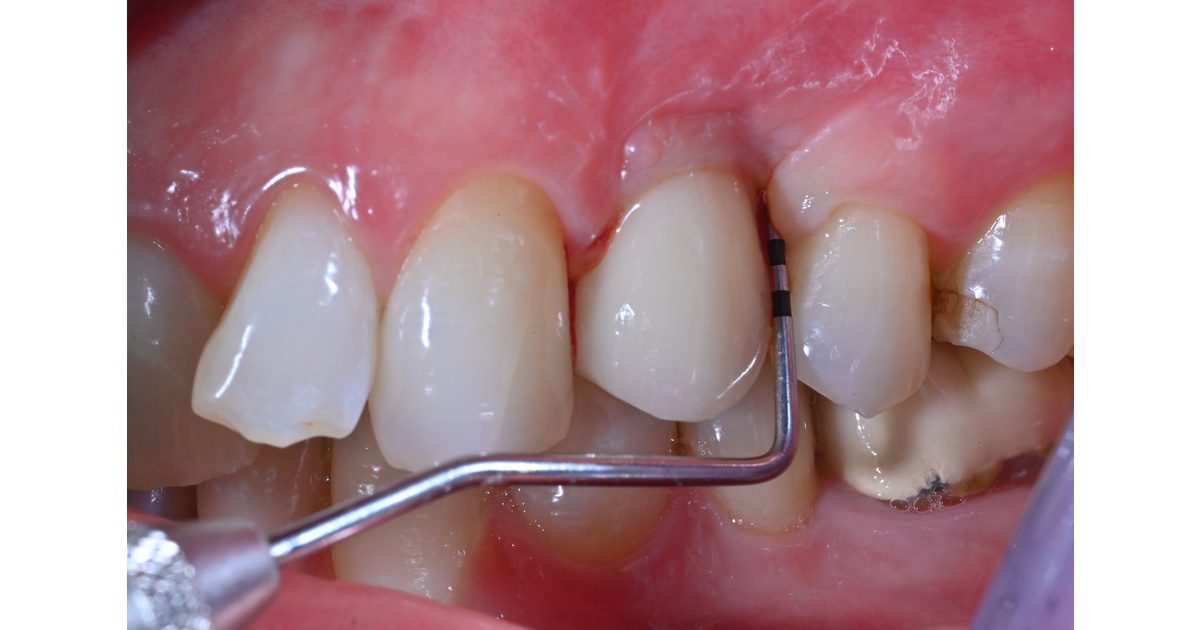

Vedlikeholds- og behandlingsstrategier for implantatpasienter med mucositt og peri-implantitt

Dette webinar tar for seg vedlikeholds- og behandlingsstrategier for implantatpasienter med mucositt og peri-implantitt, med tanke på å kunne oppnå et optimalt langtidsresultat. Målet er at du som kursdeltaker skal komme tilbake til klinikken og føle deg bedre rustet til å håndtere implantatkomplikasjoner og være tryggere på hvordan du kan unngå katastrofen. Du får med deg nye verktøy i din kliniske portefølje.